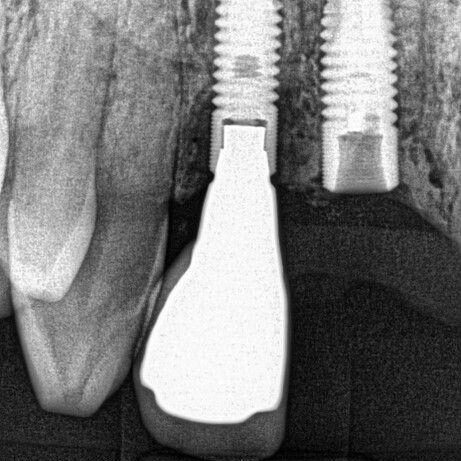

ULTRASONICS: Complications of Abutment Screw Retrieval Secondary to Prior Ultrasonic Attempts

There has been much written on the use of ultrasonics in retrieving fractured screw fragments, which I didn’t think a lot about until May of 2023, as it has not been a part of my fractured screw retrieval algorithm.